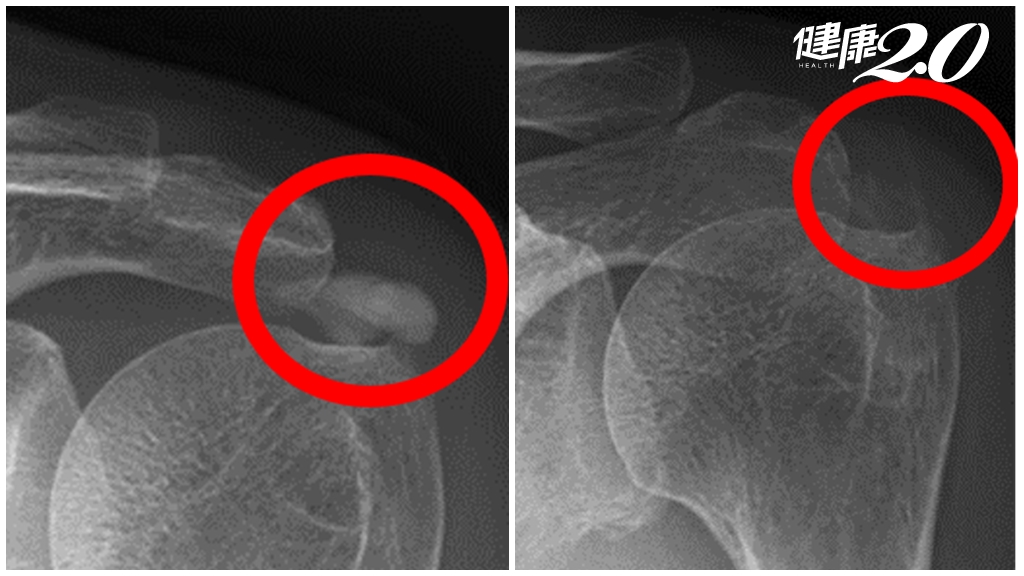

鍾玉軒醫師指出,李先生因為第三、四、五節脊椎狹窄病變,退化造成骨頭、韌帶增生,而讓腔式變窄,這是中高齡者常見的退化疾病,退化狹窄會直接壓迫腰椎或薦椎的神經根,進而引起發炎導致麻痛,連如廁都相當不便,像是排尿的時候會感覺不到,符合馬尾症候群的壓迫症狀。

雖然李先生退化情況拖延相當多年,嘗試各種保守治療無效,但評估其狀況尚不需打骨釘治療,建議他施行微創脊椎內視鏡減壓手術治療,術後只留下2個0.5公分小傷口,讓連打針也恐懼的李先生不需承受大傷口或多道傷口的疼痛。

而李先生的手術內容為第三、四腰椎跟第四、第五腰椎,總共兩節的脊椎內視鏡減壓手術,主要是移除壓迫在神經上面肥厚的黃韌帶以及增生的骨刺,並沒有去移除椎間盤。此為脊椎內視鏡部分(單側)椎板切除手術,雙側黃韌帶移除手術。